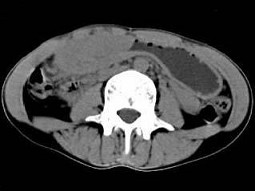

根据所提供的图像,最可能的诊断为()

• A.胃淋巴瘤

• B.胃癌

• C.胃炎性病变

• D.胃平滑肌瘤

• E.间质瘤